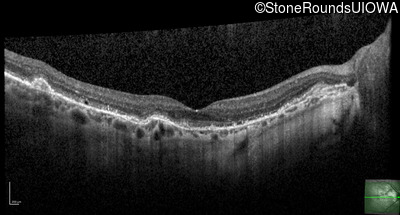

Optical Coherence Tomography - Right - 20/25 +1

Exemplar / OCT Stack